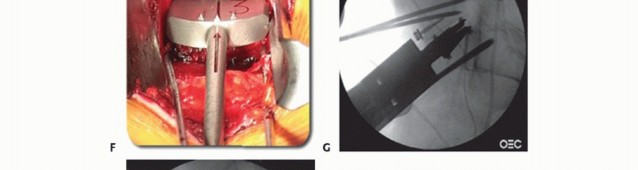

Under fluoroscopic guidance, determine the midline on a true AP image of the vertebral body above or

below the disc (TECH FIG 5A). A bone screw may be inserted as a reference.

Sizing guides are trialed to fill the entire footprint of the endplate (TECH FIG 5B). Height and lordosis are then set using trial wedges (TECH FIG 5C-E) and should match the resected gap and preoperative templating.

- TECH FIG 5 • A. True AP fluoroscopic image. The distance between the midpoint of the vertebra and the pedicles should be the same. The cortical margins of the pedicles themselves should be the same size (ensuring the spine is not rotated). Finally, the spinous processes should bisect the vertebra. The spinous processes are the least reliable landmark as they can be malformed, especially at L5 and S1. B. A sizing guide, or “lollipop,” demonstrates how well the endplate will be covered by the final implant. The largest size that allows good peripheral endplate coverage in both the sagittal and coronal planes is desired. C-E. Using radiolucent trial wedges of varying height and lordosis allows the final device to be individualized to the patient's anatomy. F. Introduction of the channel cutter into the disc space. G. Lateral fluoroscopic image showing implant insertion. The insertion instruments are still connected, which allows for fine adjustment to the final positioning. H,I. Lateral and AP fluoroscopic images of the final TDR placement with all of the instruments removed. The final implant should be in the center of the vertebral

body on the AP image and in the center (sagittal midline) or just posterior to the center of the vertebral body on the lateral image. (B-E: Courtesy of DePuy Spine, Raynham, MA.)

An implant-specific chisel is then directed straight posteriorly through the bodies to cut a groove for the keel or teeth that align the implant and prevent rotation (TECH FIG 5F) and the final implant inserted (TECH FIG 5G-I).